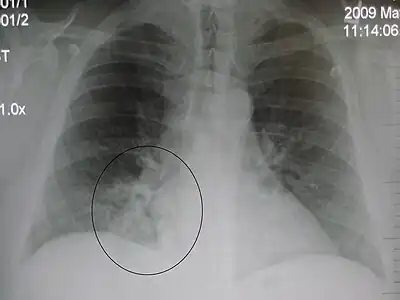

AP CXR showing right lower lobe pneumonia